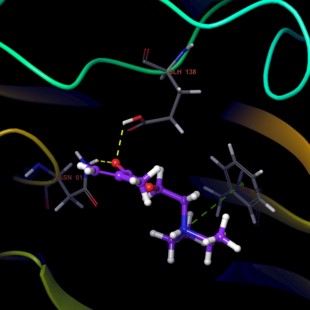

清北博士團(tuán)隊(duì)虛擬篩選 蛋白對(duì)接 網(wǎng)路藥理學(xué) 動(dòng)力學(xué)模擬 分子對(duì)接

清北博士團(tuán)隊(duì)虛擬篩選 蛋白對(duì)接 網(wǎng)路藥理學(xué) 動(dòng)力學(xué)模擬 分子對(duì)接由淘寶網(wǎng)為您挑選。折后價(jià)格4.95元,已有0人購買,選自掌柜鵬飛科技 。

?小紅書推薦?清北博士團(tuán)隊(duì)虛擬篩選 網(wǎng)路藥理學(xué) 動(dòng)力學(xué)模擬 分子對(duì)接 蛋白對(duì)接,所屬其它設(shè)計(jì)服務(wù)分類,由淘寶網(wǎng)挑選推薦!小紅書抖音網(wǎng)紅同款!哪里有賣清北博士團(tuán)隊(duì)虛擬篩選 網(wǎng)路藥理學(xué) 動(dòng)力學(xué)模擬 分子對(duì)接 蛋白對(duì)接和多少錢質(zhì)量怎么樣?。 照片精修服務(wù) ps設(shè)計(jì) 圖片處理 藝術(shù)照婚紗照精修 相冊(cè)設(shè)計(jì)服務(wù) 代寫施工組織設(shè)計(jì)土建橋梁園林深基坑高支模市政工程施工方案編寫 專業(yè)做標(biāo)書投標(biāo)物業(yè)采購餐飲服務(wù)技術(shù)標(biāo)施工組織設(shè)計(jì)方案競標(biāo)南寧 訂 名片設(shè)計(jì)烘焙店專用廣告宣傳卡片美容院開業(yè)家政服務(wù)小卡電子版 專業(yè)做標(biāo)書投標(biāo)采購服務(wù)技術(shù)標(biāo)施工組織設(shè)計(jì)方案競標(biāo)代做呼和浩特 函數(shù)設(shè)計(jì)圖表定制 excel表格制作數(shù)據(jù)處理分析vba代做宏編程序公式 C4D軟件2025 服務(wù)OC渲染器材質(zhì)球預(yù)設(shè)包插件 2024建模設(shè)計(jì)遠(yuǎn)程安裝 平面廣告海報(bào)設(shè)計(jì)制作封面主圖詳情頁宣傳單畫冊(cè)ps做圖修圖片p圖 2020設(shè)計(jì)軟件 遠(yuǎn)程安裝 2022 2021 2024 pr2025 稿定設(shè)計(jì)會(huì)員個(gè)人商用稿定設(shè)計(jì)會(huì)員搞定 稿定設(shè)計(jì)vip會(huì)員周月年卡 logo設(shè)計(jì)原創(chuàng)商標(biāo)品牌企業(yè)公司店標(biāo)志餐飲vi卡通字體圖標(biāo)名片門頭 下載字體 以圖找字體 做圖改字 包 字體安裝 代找字體 查找字體 字體識(shí)別查找ps字體AI字體pr代找字體下載字體查找中英文日韓 2022 Zemax OpticStudio光學(xué)設(shè)計(jì)軟件遠(yuǎn)程安裝 服務(wù)2019 2024 2023 設(shè)計(jì)辦公禮品個(gè)性 化定制服務(wù) 幸福我做主96小店 我